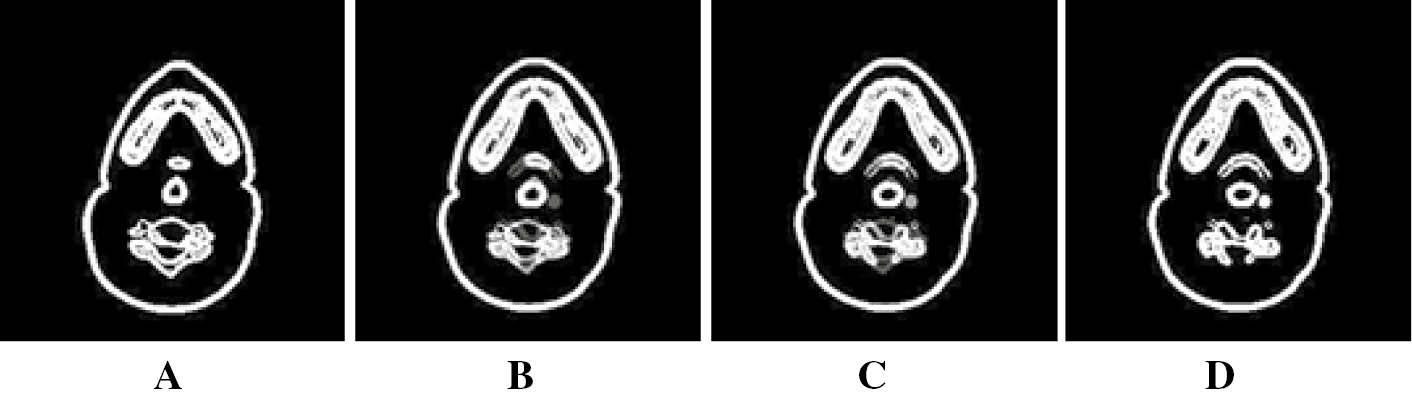

Phase Field segmented results of a human head CT. (A–D) corresponds to segmentation results of images in Figure 2.

In the MCR-based interpolation method, the optimized displacement field for both horizontal and vertical directions is calculated, which helps in providing sharper and accurate results than linear and REG-based interpolation. We have chosen time step τ=0.05 and the regularization parameter α=100. The average computational time (30.73 s) for MCR interpolation is longer than the linear interpolation but less than the REG-based interpolation. For both REG- and MCR-based interpolation, iterations were stopped when the relative error was below 10−3. The reconstructed slices 2 and 3 between the two segmented selected slices 1 and 4 using linear, REG-based, and MCR-based interpolations are shown in Figures 4–6, respectively, for a subjective comparison. Also, it is important to note that the sensitivity (95.802%) is improved on par with specificity (95.901%) in the MCR interpolation along with the accuracy and PSNR with minimum MSE. The average performance analysis with respect to the number of slices re-created between the finalized segmented slice set using the interpolation methods discussed above is given in Table 4 for a more detailed understanding. As stated earlier, the number of slices re-created is limited to a maximum of three. As the number of slices re-created increases, there is a corresponding decrease in accuracy and PSNR with an increase in MSE. This is one of the reasons for limiting the number of slices to be re-created.